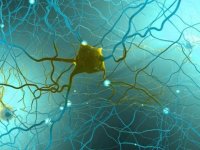

Korkutan korona uyarısı: Adeta hedef tahtasıKoronavirüsün etkilerine yönelik açıklamalarda bulunan Kardiyoloji Uzmanı Prof. Dr. Cevat Şekuri, koronavirüsün tüm dokuları ve damarsal yapıları etkilediğini belirtti. "Kalp bu hastalıkta adeta hedef tahtası, Covid-19 virüsü karşısında kırılgan bir organ03 Aralık 2020 Perşembe 13:50 Koronada en çok görülen belirtinin kaynağı ortaya çıktı. Nedeni bir türlü bulunamıyorduBilim insanları, uzun süreli yeni tip korona virüs hastalarında görülen yorgunluk ve ağrının sebebini ilk kez ortaya koydu. MRI ve ultrason tekniklerini birleştirerek elde edilen cihaz, hastada sinir hasarı bulursa, hasta nöroloğa görünecek03 Aralık 2020 Perşembe 10:39

Koronada en çok görülen belirtinin kaynağı ortaya çıktı. Nedeni bir türlü bulunamıyorduBilim insanları, uzun süreli yeni tip korona virüs hastalarında görülen yorgunluk ve ağrının sebebini ilk kez ortaya koydu. MRI ve ultrason tekniklerini birleştirerek elde edilen cihaz, hastada sinir hasarı bulursa, hasta nöroloğa görünecek03 Aralık 2020 Perşembe 10:39 DSÖ: Dünyanın 3-4 koronavirüs aşısından daha fazlasına ihtiyacı varDünya Sağlık Örgütü Acil Durumlar Programı Direktörü Mike Ryan, yeni tip koronavirüs (Covid-19) aşı çalışmalarına ilişkin, "Durmamalıyız. 3-4 aşıdan fazlasına ihtiyacımız var. Üretimi artırmalıyız, fiyatı düşürmeliyiz. Tek doz aşıya ihtiyacımız var" dedi03 Aralık 2020 Perşembe 10:34